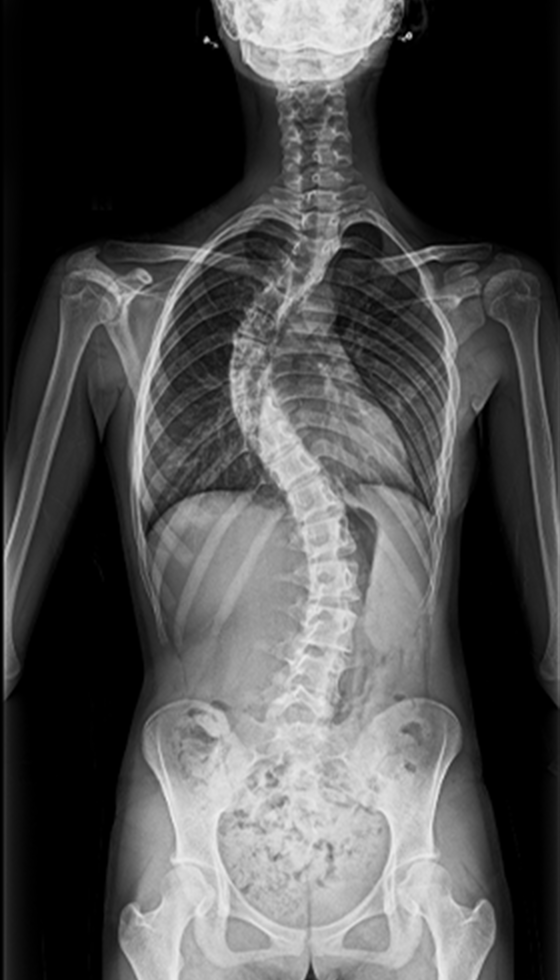

Gallery : Before - After

After

Before